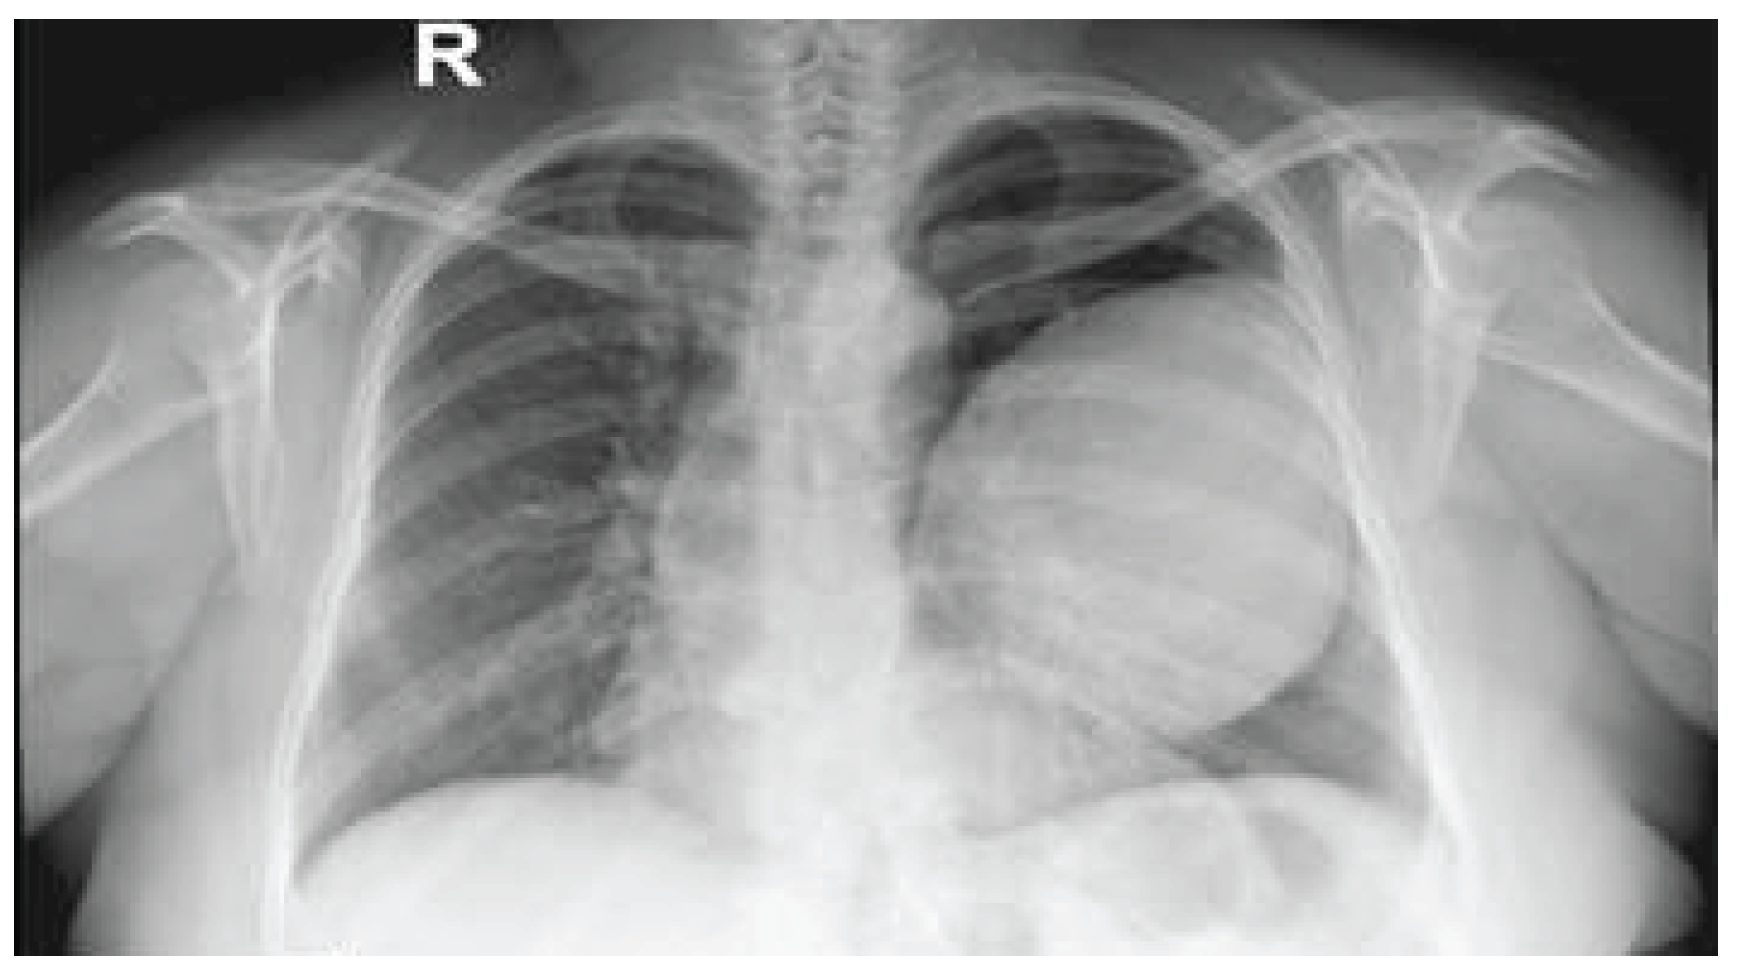

Case